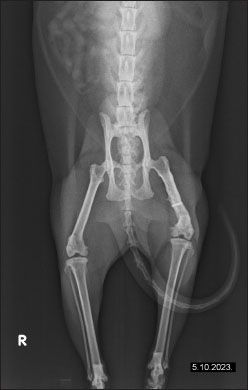

The owner reported continuous improvement, noting that the cat is increasingly bearing weight on the left hind limb, showing fewer signs of pain, and displaying an improved disposition. Follow-up radiographs revealed improvement in the condition of the femur post-therapy (Fig. 4). There is a noticeable improvement in bone structure, indicating enhanced healing and remodeling processes. After 2 months of intensive therapy and visible clinical improvement, the intervals between treatments were further extended. The radiograph shows the bone structure to be more consolidated, indicating effective recovery and remodeling (Fig. 5). Overall, the imaging suggests a positive outcome following treatment. In agreement with the owner, the treatments have continued on a monthly basis, and the cat continues to show progress.

Fig. 5. Radiographic evidence of consolidated bone structure and reduced medullary transparency following 25 sessions of LT.